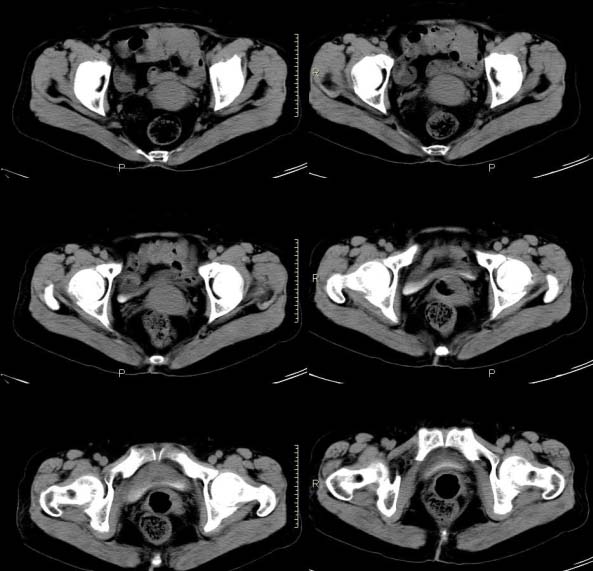

女,63岁,绝经15年,从阴道内有液体流出约1月余,且带有血,患者一般情况很差,在家属搀扶下行走。请大家看看是子宫病变还是宫颈病变?

子宫颈体积增大,宫颈壁不均匀性增厚,且不均匀性强化。考虑为宫颈ca。

子宫颈内见低密度影,外形不规则,不均匀强化,考虑占位,子宫颈癌可能性大。